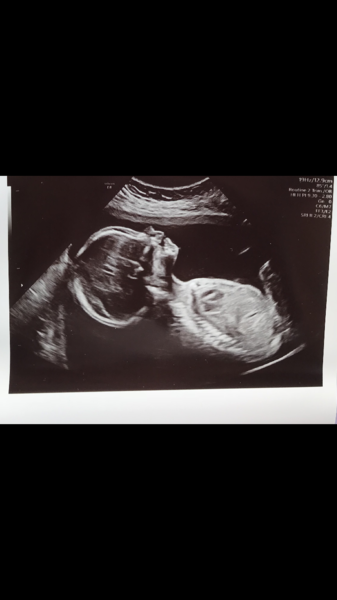

Anatomy scan went well this morning; nothing was brought to our attention anyway. Still team pink and am just so, so grateful everything is moving in the right direction

So glad to see everyone’s scans going well. I also had mine and everything looked perfect, couldn’t believe how clear the picture was. Midwife said I have strong ab muscles so she’s sitting down by my pelvis still 💕

So lovely to see everyone's clear scan pics! My 20 week scan is on Tuesday! I am v scare-cited. My husband can't come so my mum is coming. I think she's quite looking forward to it. I am hoping everything is ok, of course, but also that maybe the husband will book a private scan so he can come (and I'll get to see baby again!).